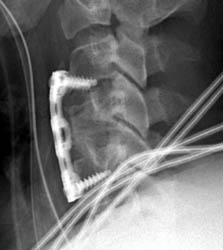

Screw in disc space

43 year old male with moderate myelopathy referred to C3,4 and severe myelopathy

in C5,6 distributions underwent C4 vertebrectomy and C3-4, C4-5 discectomies.

Immediate

post-operative lateral radiograph demonstrating cortical fixation screws traversing the C3-4

disc space.